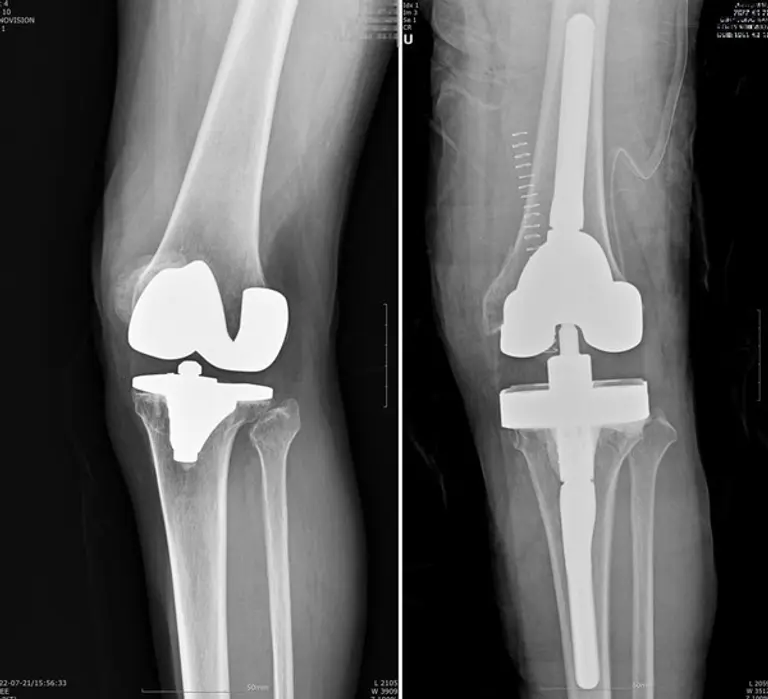

인공관절 재치환술은 A씨처럼 외상으로 인해 문제가 생기거나, 인공관절을 오래 써서 닳아 흔들리거나 염증, 감염 등으로 인해 인공관절이 제 기능을 하지 못하고 통증을 유발하는 경우 시행하게 된다.

인공관절 재치환술은 많은 경우 골 소실 및 연부조직 손상을 동반하기 때문에 수술 자체도 까다롭고 처음 수술보다 결과가 좋지 않은 경우도 있다. 또 대부분 80세 이상의 고령 환자가 많아 만성질환 합병증의 위험도 따른다. 실제 보건복지부 지정 관절전문 연세사랑병원의 통계에 따르면 인공관절 재수술을 받은 환자 809명 중 80세 이상이 16%를 차지했다.

고용곤 연세사랑병원장(정형외과 전문의)은 “인공관절 재치환술을 위해 가장 먼저 고려할 것은 임상 경험이 풍부한 의료진을 선택하는 것과 만성 질환에 대비할 수 있는 내과 전문의가 상주하는 병원을 찾는 것"이라며 “인공관절 재치환술은 1차 수술에 비해 까다롭고 시간도 오래 걸리는 수술이다. 의료진의 실력에 따라 천차만별의 결과를 낳기 때문에 의사의 임상 경험이 풍부한지 따져봐야 한다”고 조언했다.